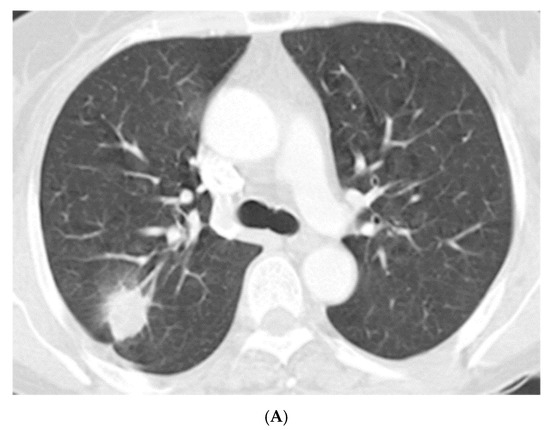

Radiologic characteristics of NTM nodules are summarized in Table 2. The median long-axis diameter of 49 nodules on chest CT was 18.0 mm (IQR 12.5–28.5 mm), and approximately half (49%) were located in the upper lobes. Most (82%) were located in the subpleural area (Figure 1A). Spiculation and pleural invagination were observed at 80% and 73% of the nodules, respectively. About a third of the nodules (31%) had associated calcification and 3 (6%) had satellite lesions. Of the 41 nodules for which FDG-PET/CT was available, the median SUVmax was 4.9 (IQR 2.5–8.7), and 76% (31/41) of them had relatively high uptake (SUVmax > 2.5) (Figure 1B).

Figure 1.

(A) A 56-year old female with a solitary pulmonary nodule. Chest computed tomography showed a 23-mm-sized oval nodule at the posterior segment of right upper lobe. (B) Positron emission tomography with fluorodeoxyglucose (FDG) revealed a nodule with increased FDG uptake in the right upper lobe mimicking malignancy.